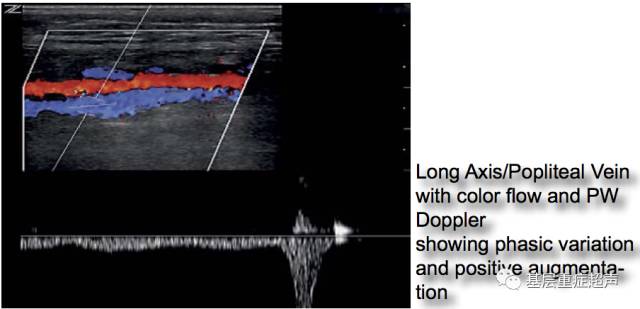

压迫小腿肌肉可以在超声图像上观察到近端静脉更加充盈。可用脉冲多普勒或彩色多普勒更好的观察静脉充盈,超声观察到静脉充盈,能够说明从远端的压迫部位至探头位置的静脉是通畅的。注意观察随着呼吸的静脉血流时相变化(吸气时收缩,呼气时扩张)。

腘静脉检查

在腘窝处横向放置探头,可观察到与腘动脉及腘静脉。在彩色多普勒模式下,通过压迫腓肠肌促进回流,观察腘窝充盈。彩色多普勒可观察到随呼吸的时相变化